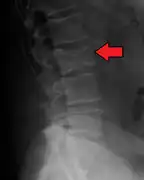

Pathological fracture of the lumbar spine due to multiple myeloma

The diagnostic examination of a person with suspected multiple myeloma typically includes a skeletal survey. This is a series of X-rays of the skull, axial skeleton, and proximal long bones. Myeloma activity sometimes appears as "lytic lesions" (with local disappearance of normal bone due to resorption). And on the skull X-ray as "punched-out lesions" (pepper-pot skull). Lesions may also be sclerotic, which is seen as radiodense.[47] Overall, the radiodensity of myeloma is between −30 and 120 Hounsfield units (HU).[48] Magnetic resonance imaging is more sensitive than simple X-rays in the detection of lytic lesions, and may supersede a skeletal survey, especially when vertebral disease is suspected. Occasionally, a CT scan is performed to measure the size of soft-tissue plasmacytomas. Bone scans are typically not of any additional value in the workup of people with myeloma (no new bone formation; lytic lesions not well visualized on bone scan).